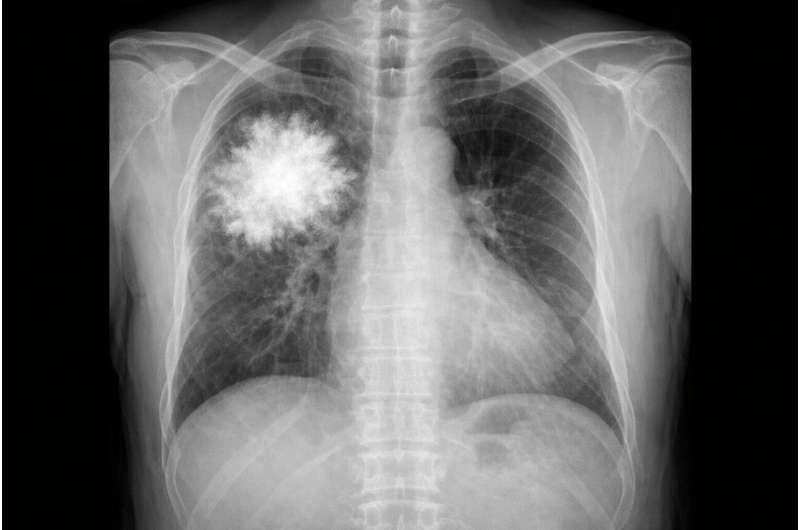

研究人员进一步训练了一个 仅基于文本 的模型,它完全无法访问任何视觉数据,却被用来回答关于胸部X光检查的问题。

令人意外的是,这个纯文本模型在标准胸部X光问答基准上,表现竟然优于多款顶级多模态AI系统,甚至超过人类医生。这一结果表明,当前评估体系可能在很大程度上依赖题目中的文本模式,而非真正的图像理解。